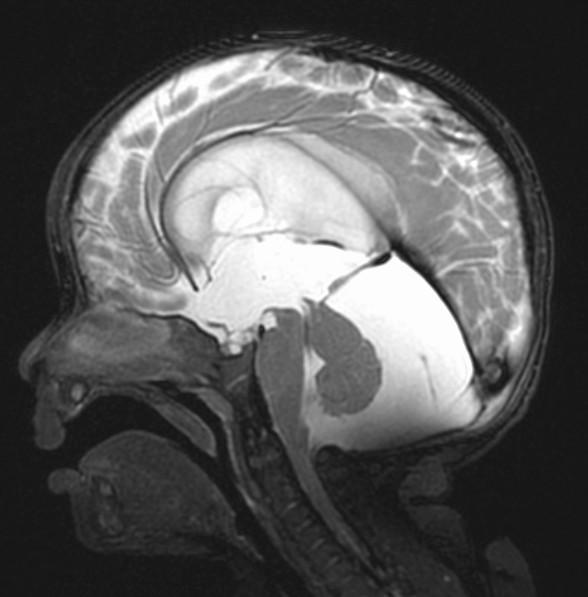

Fused hemispheres, absent or hypoplastic vermis, and superior cerebellar peduncles

Needs to have fusion of the dentate nuclei

Assn: hydrocephalus, limbic anomalies, cortical malformations, absent septum pellucidum, multiples suture synostosis

Where is the vermis? Big or small?

Do you have a normal fastigial point?

What is the abnormal horizontally oriented structure? What is the diagnosis?

Where is the vermis? Big or small? Too small…

Do you have a normal fastigial point? Yes, pointed… What is the abnormal horizontally oriented structure? the superior cerebellar peducle…

What is the diagnosis?